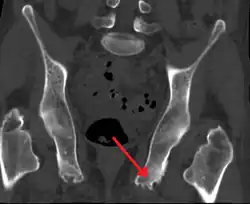

U osób nieuprawiających sportu prawdopodobnie najczęstszym czynnikiem etiologicznym są mikrourazy. Z czasem, może dodatkowo rozwinąć się tzw. ostroga piętowa, która w pojedynczych przypadkach nasila ból, uciskając okoliczne tkanki. Często jednak, widoczne na radiogramie ostrogi piętowe są nieme klinicznie.